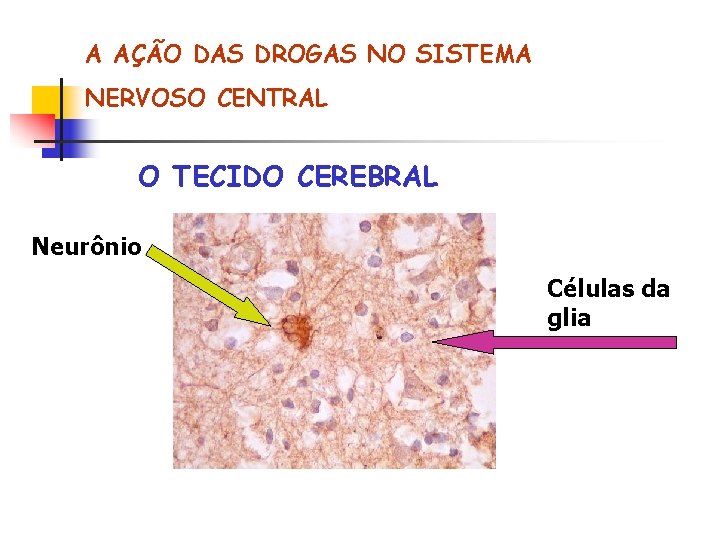

A AÇÃO DAS DROGAS NO SISTEMA NERVOSO CENTRAL O TECIDO CEREBRAL Neurônio Células da glia